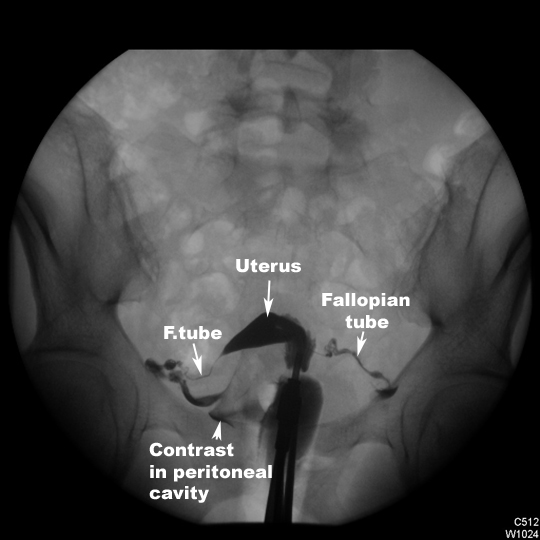

Hysterosalpingogram. Click the image for labeling.